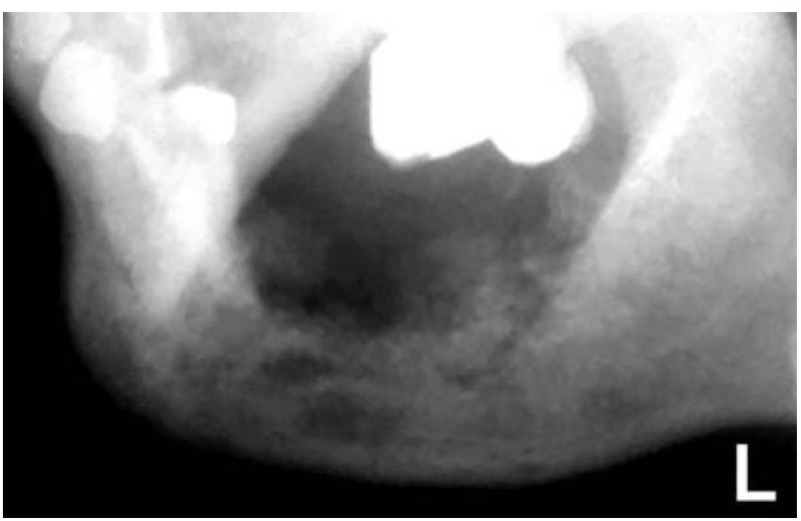

HOẠI TỬ XƯƠNG HÀM SAU XẠ TRỊ

CHẨN ĐOÁN ?